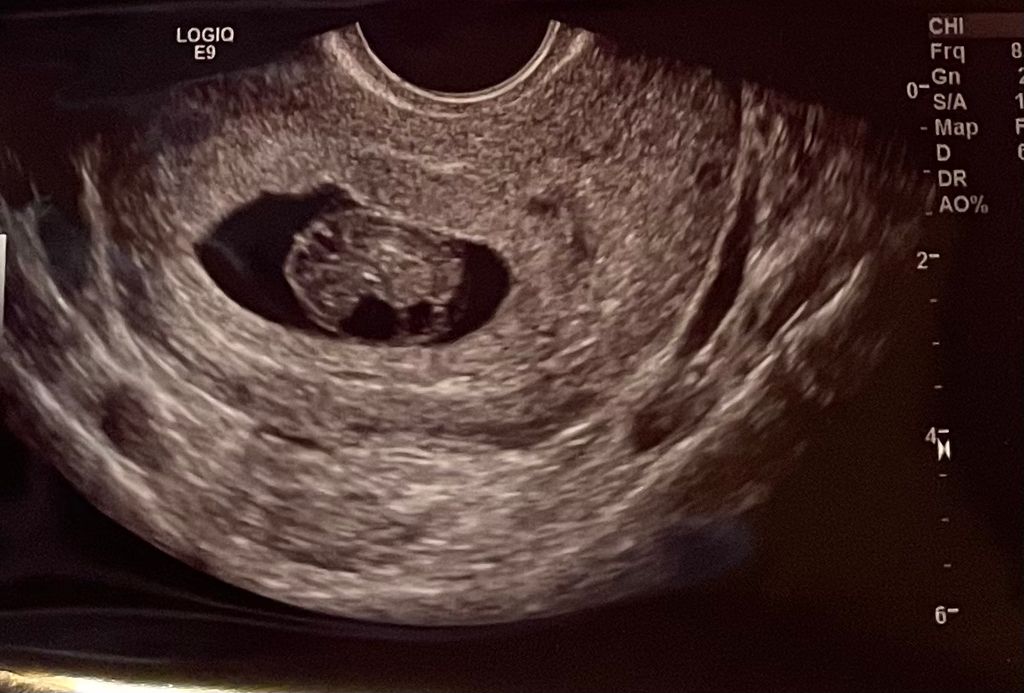

Ultrasound at 9 weeks! Baby moving like crazy! YouTube

9 Weeks Pregnant Ultrasound Baby's Heartbeat YouTube Is It Normal To Not Hear Heartbeat At 9 Weeks It's more likely to hear it around 12 weeks, although sometimes they catch. No fetal heartbeat on an early. The baby measured exactly 9 weeks. You can typically hear your baby's heartbeat with a fetal doppler stethoscope between weeks 9 and 12 of pregnancy. What no fetal heartbeat on an early ultrasound means. No fetal heartbeat on an ultrasound: I. Is It Normal To Not Hear Heartbeat At 9 Weeks.

Our 9 week ultrasound with heartbeat and movement! YouTube Is It Normal To Not Hear Heartbeat At 9 Weeks You can typically hear your baby's heartbeat with a fetal doppler stethoscope between weeks 9 and 12 of pregnancy. I have no cramping or bleeding and my. The sonographer confirmed that growth stopped around 6+6 and she couldn't detect a heartbeat today (should have been 9 weeks. I was told today during my first internal ultrasound that my baby had. Is It Normal To Not Hear Heartbeat At 9 Weeks.

Pregnancy ultrasound at 8 to 9 weeks with heart beat YouTube Is It Normal To Not Hear Heartbeat At 9 Weeks You can typically hear your baby's heartbeat with a fetal doppler stethoscope between weeks 9 and 12 of pregnancy. What no fetal heartbeat on an early ultrasound means. That's totally normal not to hear it at 9 weeks with the doppler. But the truth is, at least for most cases, no heartbeat at 9 weeks pregnant is normal. My beta. Is It Normal To Not Hear Heartbeat At 9 Weeks.

Ultrasound at 9 weeks! Baby moving like crazy! YouTube Is It Normal To Not Hear Heartbeat At 9 Weeks What no fetal heartbeat on an early ultrasound means. My beta hcg was always normal and i was still nauseous. The baby measured exactly 9 weeks. That's totally normal not to hear it at 9 weeks with the doppler. Then when will your baby’s heartbeat be detected, and what will it. The sonographer confirmed that growth stopped around 6+6 and. Is It Normal To Not Hear Heartbeat At 9 Weeks.

Early Ultrasound 9 weeks 2 days Coolest Family on the Block Is It Normal To Not Hear Heartbeat At 9 Weeks 9 weeks and no heartbeat update. It's more likely to hear it around 12 weeks, although sometimes they catch. That's totally normal not to hear it at 9 weeks with the doppler. I was told today during my first internal ultrasound that my baby had no heartbeat. The baby measured exactly 9 weeks. What no fetal heartbeat on an early. Is It Normal To Not Hear Heartbeat At 9 Weeks.